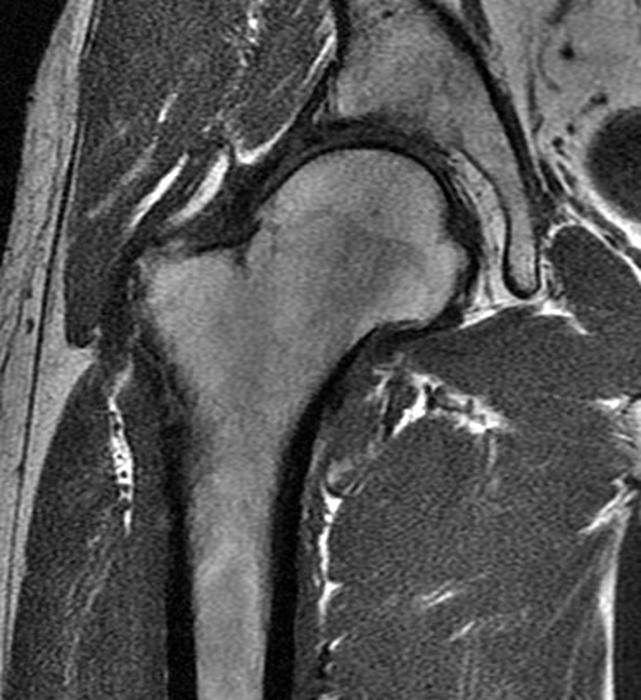

Femoroacetabular impingement camtype Image Cam-Type Femoroacetabular Impingement The restricted motion damages cartilage and can cause a labral tear, resulting in pain and arthritis in young adults. In some cases, physical activity may cause this growth to occur. Learn about the causes, symptoms, and treatments of fai, a condition in which extra bone grows along the hip joint and causes pain and damage. In some cases, the ball. Cam-Type Femoroacetabular Impingement.

CAM type femoroacetabular impingement with fracture Image Cam-Type Femoroacetabular Impingement In some cases, the ball is too. Find out the symptoms, diagnosis and treatment options for this condition that affects hip motion and pain. This type results from a bony growth at the head of the femur. In some cases, physical activity may cause this growth to occur. The restricted motion damages cartilage and can cause a labral tear, resulting. Cam-Type Femoroacetabular Impingement.